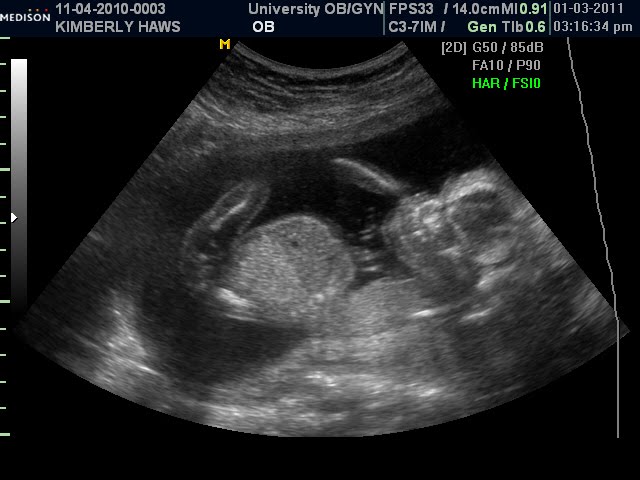

We went to have the ultrasound on Monday and found out that we will be having another boy! For Annie's sake we were hoping this one might be a little girl but we are equally as excited to be having another boy. Tyson is excited because one more and we'll have a full boys singing quartet. The doctor said the due date is still right at the end of May which surely won't come soon enough. He said everything looks healthly which we are so grateful for. We have had 3 healthy baby's so far and we consider ourselves blessed. Here is a little side profile of his head, belly, a leg and one little arm there in the background.